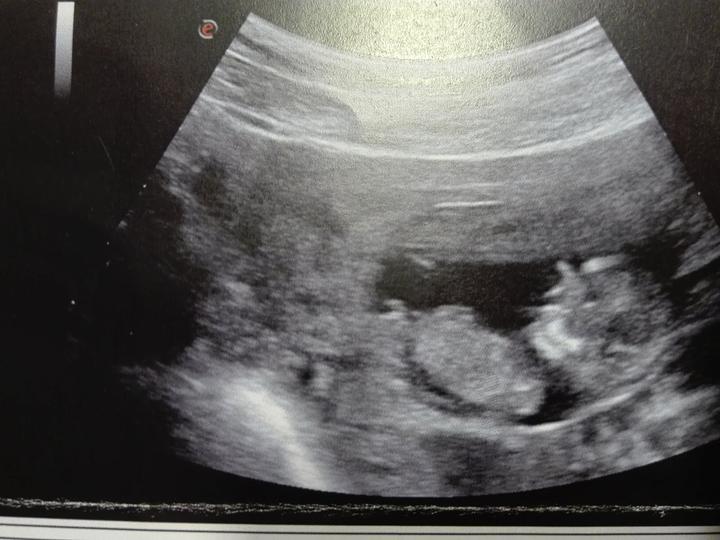

Naše zlaticko :-*